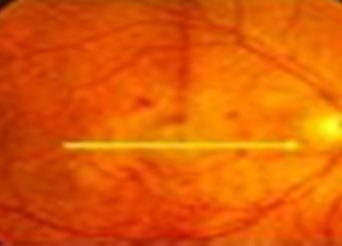

Η ωχρά κηλίδα είναι το κεντρικό τμήμα του αμφιβληστροειδή, ένα λεπτό στρώμα φωτοευαίσθητων νευρικών κυττάρων και ινών που βρίσκεται στο πίσω μέρος του οφθαλμού. Ο αμφιβληστροειδής μετατρέπει το φωτεινό ερέθισμα σε νευρικό ερέθισμα το οποίο ο εγκέφαλός μας μπορεί και αντιλαμβάνεται σαν εικόνα. Η ωχρά κηλίδα είναι υπεύθυνη για την κεντρική όραση και μας επιτρέπει […]